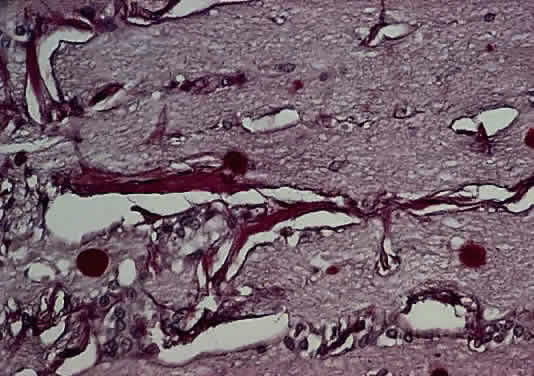

Injury to the retina or any peripheral portion of the optic nerve results in rapid ascending atrophy of the central portion. Initially, the axons at the peripheral portion swell. Retrograde degeneration of the axon then occurs, with loss of retinal ganglion cells. Clinically, there is pallor of the optic disc (Fig. 27), and early decreased fluorescence is seen with angiography. The atrophic optic nerve is surrounded by a loose sheath (Fig. 28). Microscopically, there is shrinkage of the nerve parenchyma secondary to axonal and myelin loss and gliosis (Fig. 29). Corpora amylacea accumulate in the subpial and perivascular areas (Fig. 30). With shrinkage of the nerve, the subarachnoid space is widened and the pial strands and arteriolar walls are thickened. Atrophy that is secondary to glaucoma is initially seen in the prelaminar region. Loss of astrocytes and axons results in baring of the lamina and deep excavation of the optic cup (Figs. 31 and 32).

Fig. 29. Thick collagenous pial strands in atrophic optic nerve extend around central vessels (cross-section hematoxylin and eosin staining).